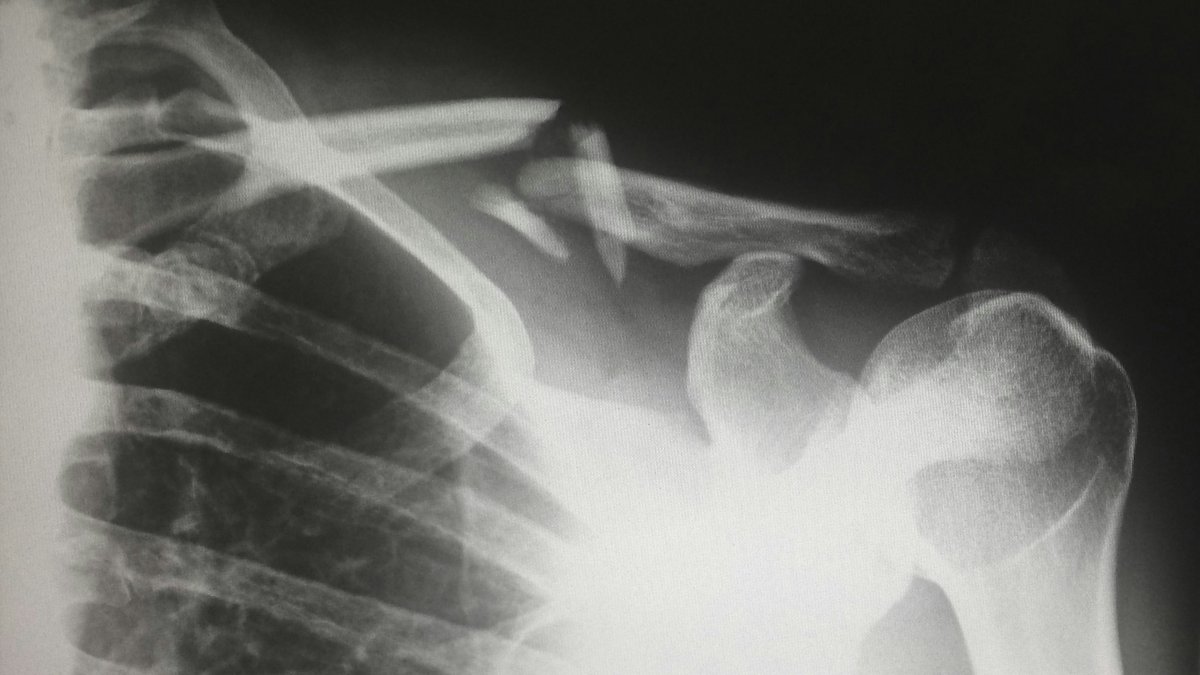

I. Les différents types de fractures

1.1 Classification selon la structure

• Fracture transverse : ligne droite perpendiculaire à l’axe de l’os

• Fracture oblique : ligne en diagonale

• Fracture spiroïde : en spirale, souvent due à une torsion

• Fracture comminutive : os fragmenté en plusieurs morceaux

• Fracture en bois vert : fréquente chez l’enfant, l’os se plie sans se casser complètement

1.2 Classification selon la gravité

• Fracture fermée : la peau reste intacte

• Fracture ouverte : l’os perce la peau